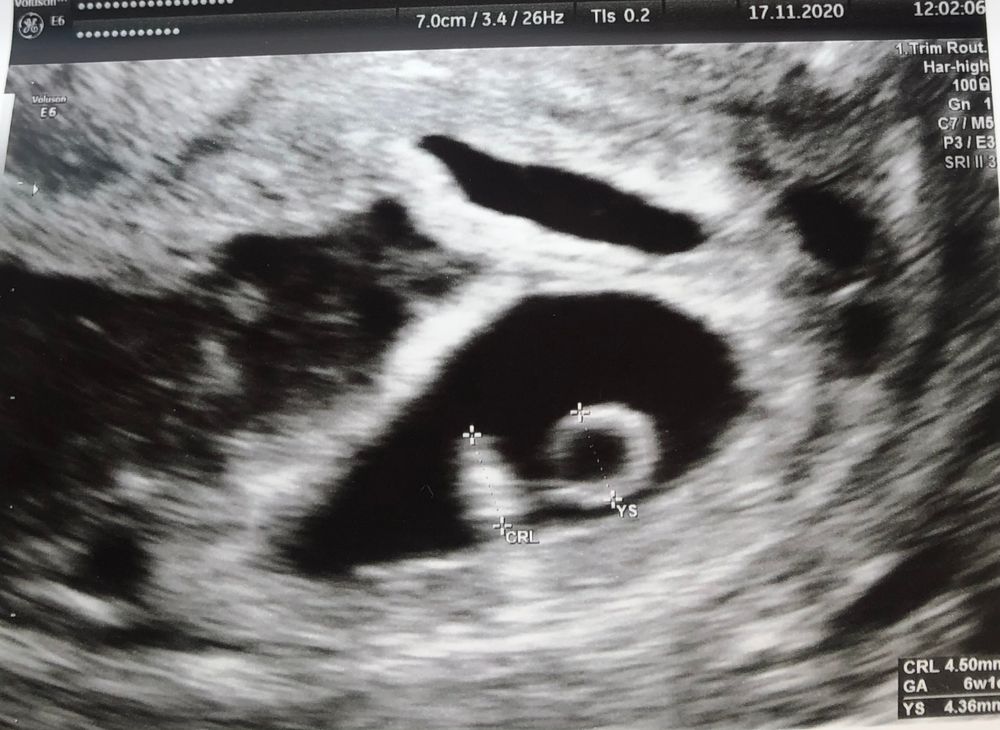

26 ДПП Узи после крови

Да,гематома.У меня была точная такая же картина)

Прогестерон  Кровит 25 дпп( 6 недель)